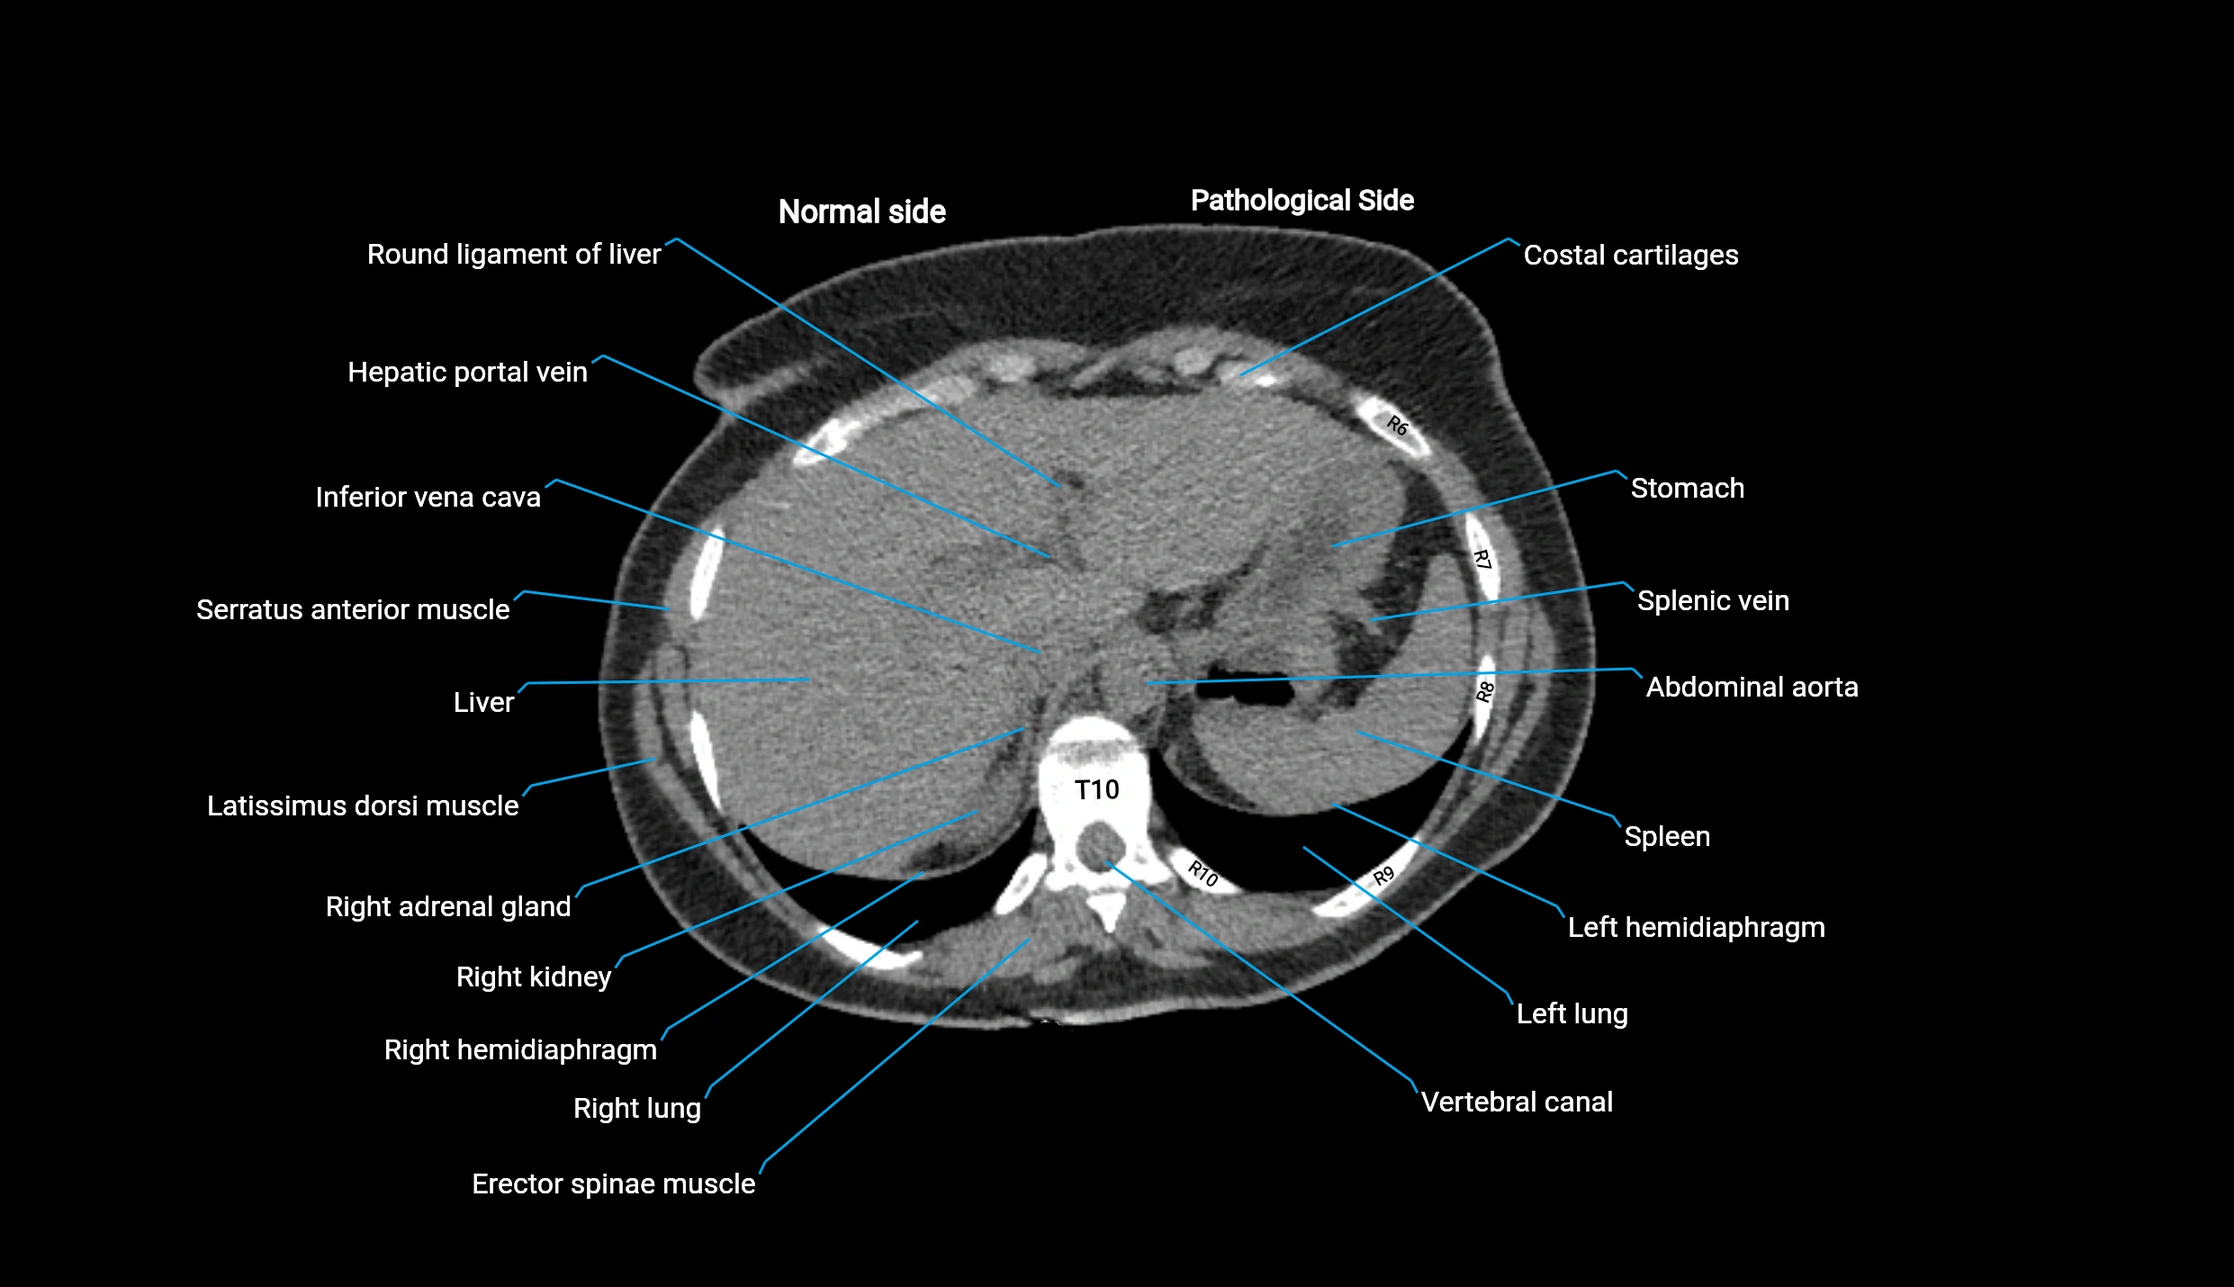

CT image

image